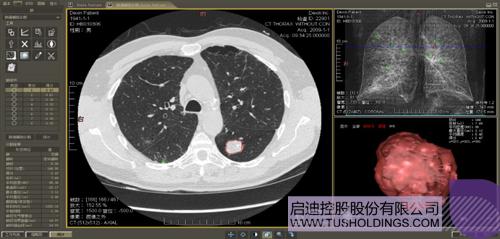

数字肺产品肺癌计算机辅助诊断

医疗影像智能分析是指运用人工智能技术、计算机视觉技术以及计算几何技术对医疗影像进行自动分析,帮助医生定位病症、分析、跟踪病情,并通过量化数据辅助医生做出诊断,目前其旗舰产品“数字肺”已经覆盖多种肺部疾病的早期检测、诊断、跟踪、术前规划等完整的医疗流程。在临床实践中,超过80%的医疗数据来自医疗影像,这些影像数据通常需要专业医生进行解读,工作的重复性高、效率偏低。如果能够运用智能影像分析技术,同时结合临床表现以及既往病例进行全面分析,那么就可以大幅度提升影像诊断效率和准确性,让专业医生的宝贵时间集中在复杂病情的诊断和治疗等环节。

数字肺——肺结节手术规划系统